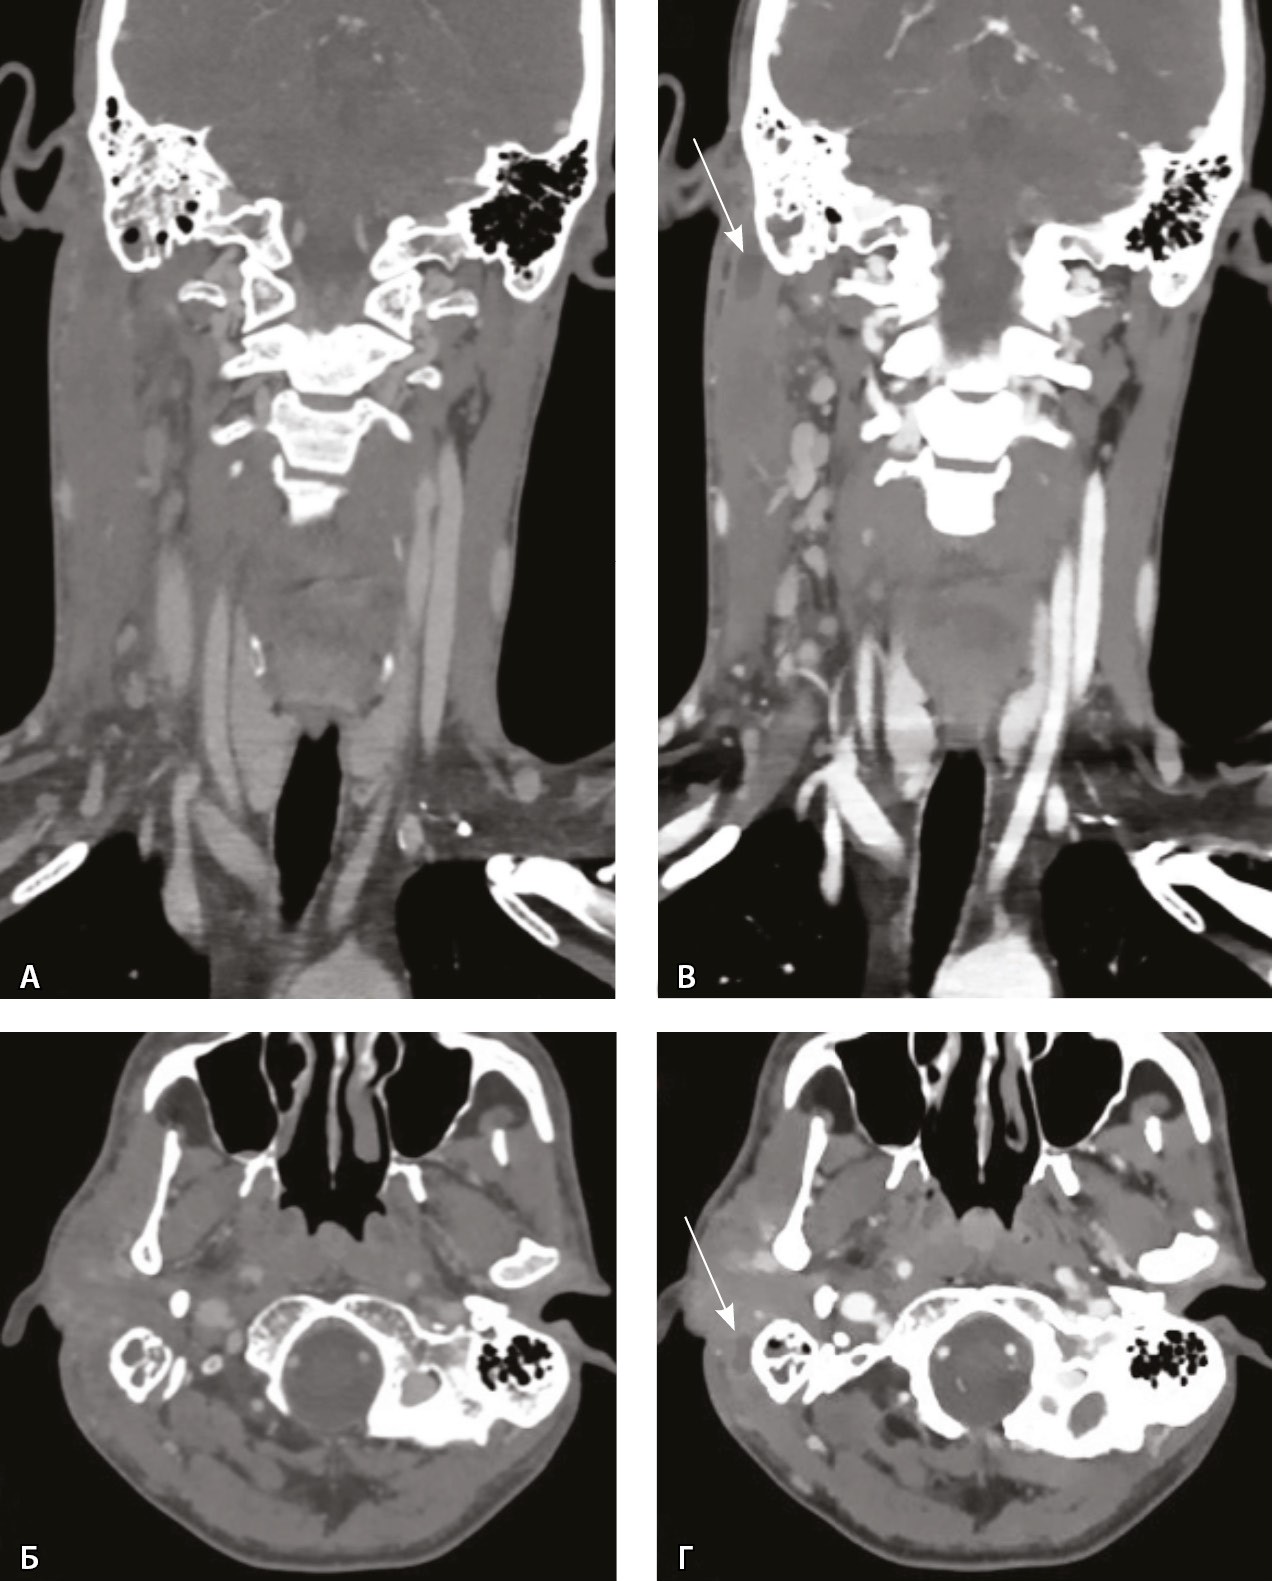

При КТ основания черепа и шеи до и после внутривенного болюсного введения йодсодержащего контрастного препарата (в рекомендуемом согласно инструкции по применению препарата объеме и с рекомендованной скоростью введения) и дальнейшем анализе сканов в абдоминальном окне начиная с уровня наружного основания черепа справа имелось явно определяемое асимметричное утолщение мягких тканей и уплотнение клетчаточных пространств. Однако на фоне утолщенных мягких тканей в режиме обычной визуализации дополнительных жидкостных образований, требующих хирургического вмешательства, не обнаружено. Так как исследование выполняли на компьютерном томографе Philips iQon Spectral CT (Philips, Нидерланды), был проведен анализ моноэнергетических изображений с низкими энергиями. Это позволило выявить в толще измененных мягких тканей на уровне сосцевидного отростка, в парафарингеальном пространстве низкоконтрастные сообщающиеся жидкостные образования – скопления гноя, которые на обычных изображениях не определялись и могли быть пропущены врачом-рентгенологом (рис. 3).

Рис. 3. Компьютерная томография шеи, венозная фаза. Фронтальная реконструкция и аксиальный скан. А, Б – обычный режим, мягкотканное окно; В, Г – моноэнергетическое изображение 40 кеВ на том же уровне: виден субпериостальный абсцесс вдоль латеральной поверхности верхушки сосцевидного отростка (стрелки), не определяемый в обычном режиме

Заключение по проведенному исследованию: правосторонний мастоидит, субпериостальный абсцесс на уровне верхушки правого сосцевидного отростка (абсцесс Бецольда), флегмона шеи справа.